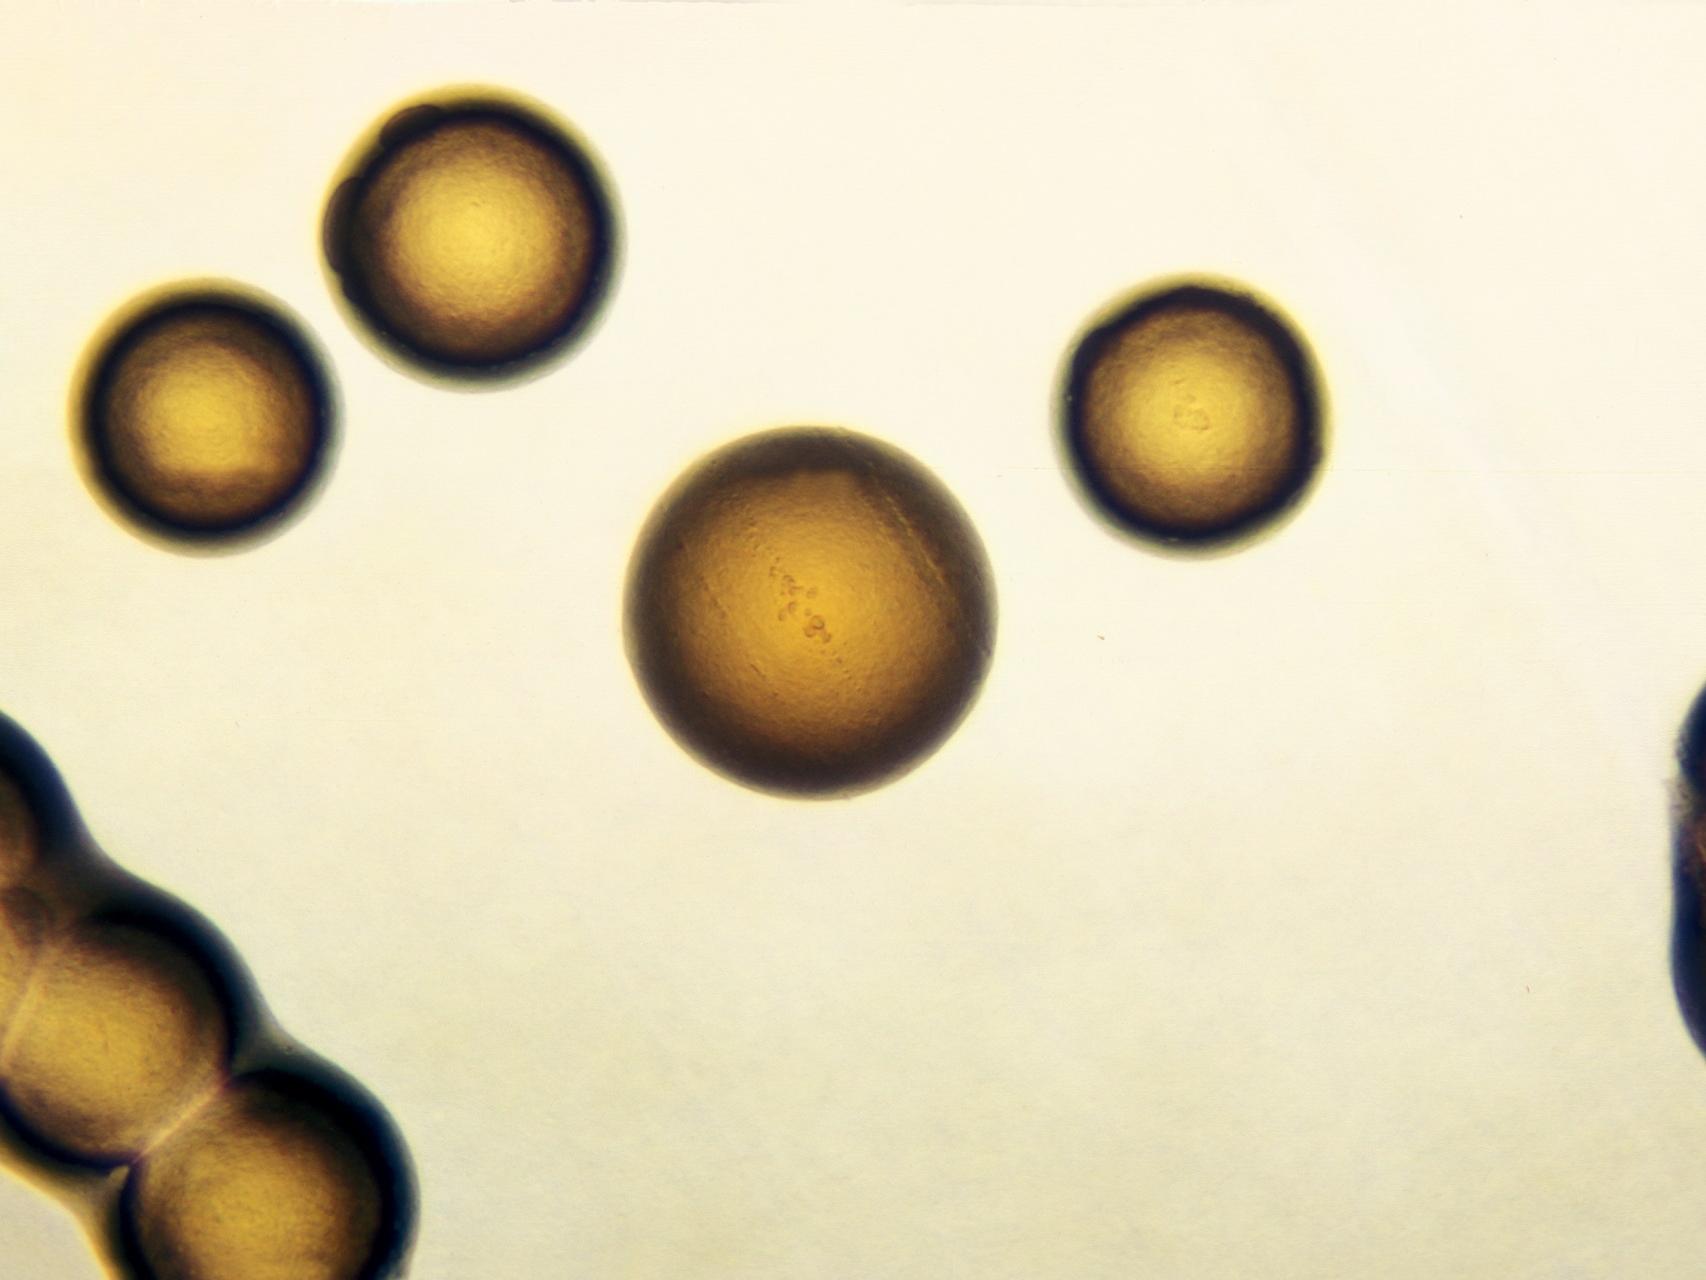

Los CDC recomiendan actualmente que la infección -causada por la bacteria Neisseria gonorrheae- se trate con una combinación de dos antibióticos: un comprimido de azitromicina y una inyección de ceftriaxona. Pues bien, según el nuevo informe, entre 2013 y 2014 el porcentaje de especímenes de gonorrea con una menor susceptibilidad a la azitromicina se ha incrementado en más de un 300%. Un "signo inquietante" de que el futuro del tratamiento actual esté en peligro.